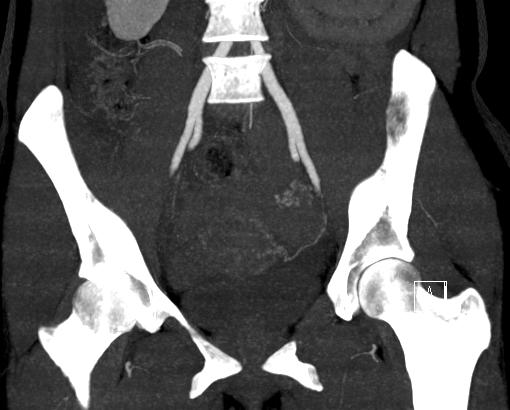

előzmény: 3 hete otthonában 6 hetes spontán vetélése zajlott. Beavatkozást nem igényelt. Tegnap délután intermittáló jellegű éles alhasi fájdalma kezdődött, hányinger kíséretében.

műtéti leírás: A hasüregben részben alvadékos vér található. A kismedencében az uterus egyenletesen megnagyobbodott, anteflexioban helyezkedik el. A vért szívóval részben eltávolítjuk ekkor észleljük, hogy a bal oldali kürtben középen kb 2 cm átmérőjű extauterin graviditás látható.